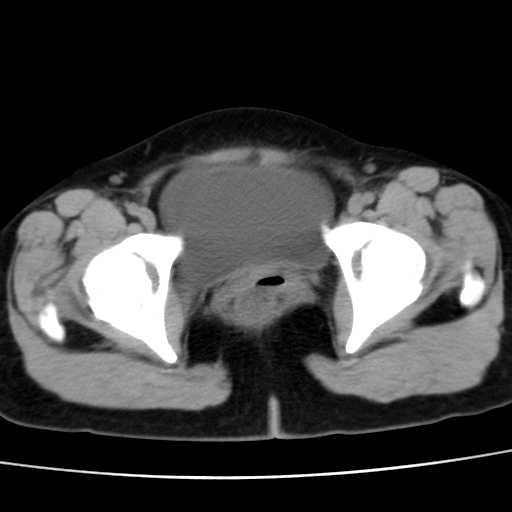

子宫多发肌瘤吗

多发性子宫肌瘤.

考虑多发子宫肌瘤,子宫直肠窝双囊性占位,另直肠周围脂肪密度增高,不知有何病史

支持考虑多发子宫肌瘤~!子宫直肠陷凹积液?

支持考虑多发子宫肌瘤~!子宫直肠陷凹积液!

子宫肌瘤,宫体部后方见液性密度影,是肠道还是子宫与直肠陷窝积液不好说,我觉得它的位置有点高

支持考虑多发子宫肌瘤!子宫直肠陷凹积液!

患者发热,而子宫直肠窝液性灶有明显边缘且局限且囊性,不除外为包裹性积液或脓肿

支持考虑多发子宫肌瘤,子宫直肠陷凹积液可能。

考虑多发子宫肌瘤

1)考虑子宫肌瘤可能性大。2)子宫后方囊性占位性病变,不排除卵巢囊肿可能。

考虑多发子宫肌瘤。子宫后方囊性占位性病变,不排除卵巢囊肿可能。